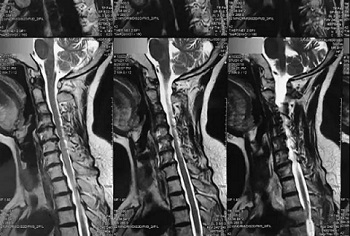

九、翻拍磁共振图像时,因为磁共振片子很大,而且一张片子上有很多图像(如下图),所以,单纯的拍一张片子,因为手机拍摄,像素以及翻拍质量不好,且放大后图像会发虚,细节看不清楚,所以,基本上是没用的,对于医生阅片来说,质量太差,不能获取图片上的有效信息。

十、因此需要将磁共振的一张片子,进行分区域局部放大拍摄,尽可能的将片子上的细节拍摄清楚,将一张磁共振片子进行分区。

十一、将分区的磁共振图像,按顺序进行拍摄,即可获取如下比较有价值的清晰图片